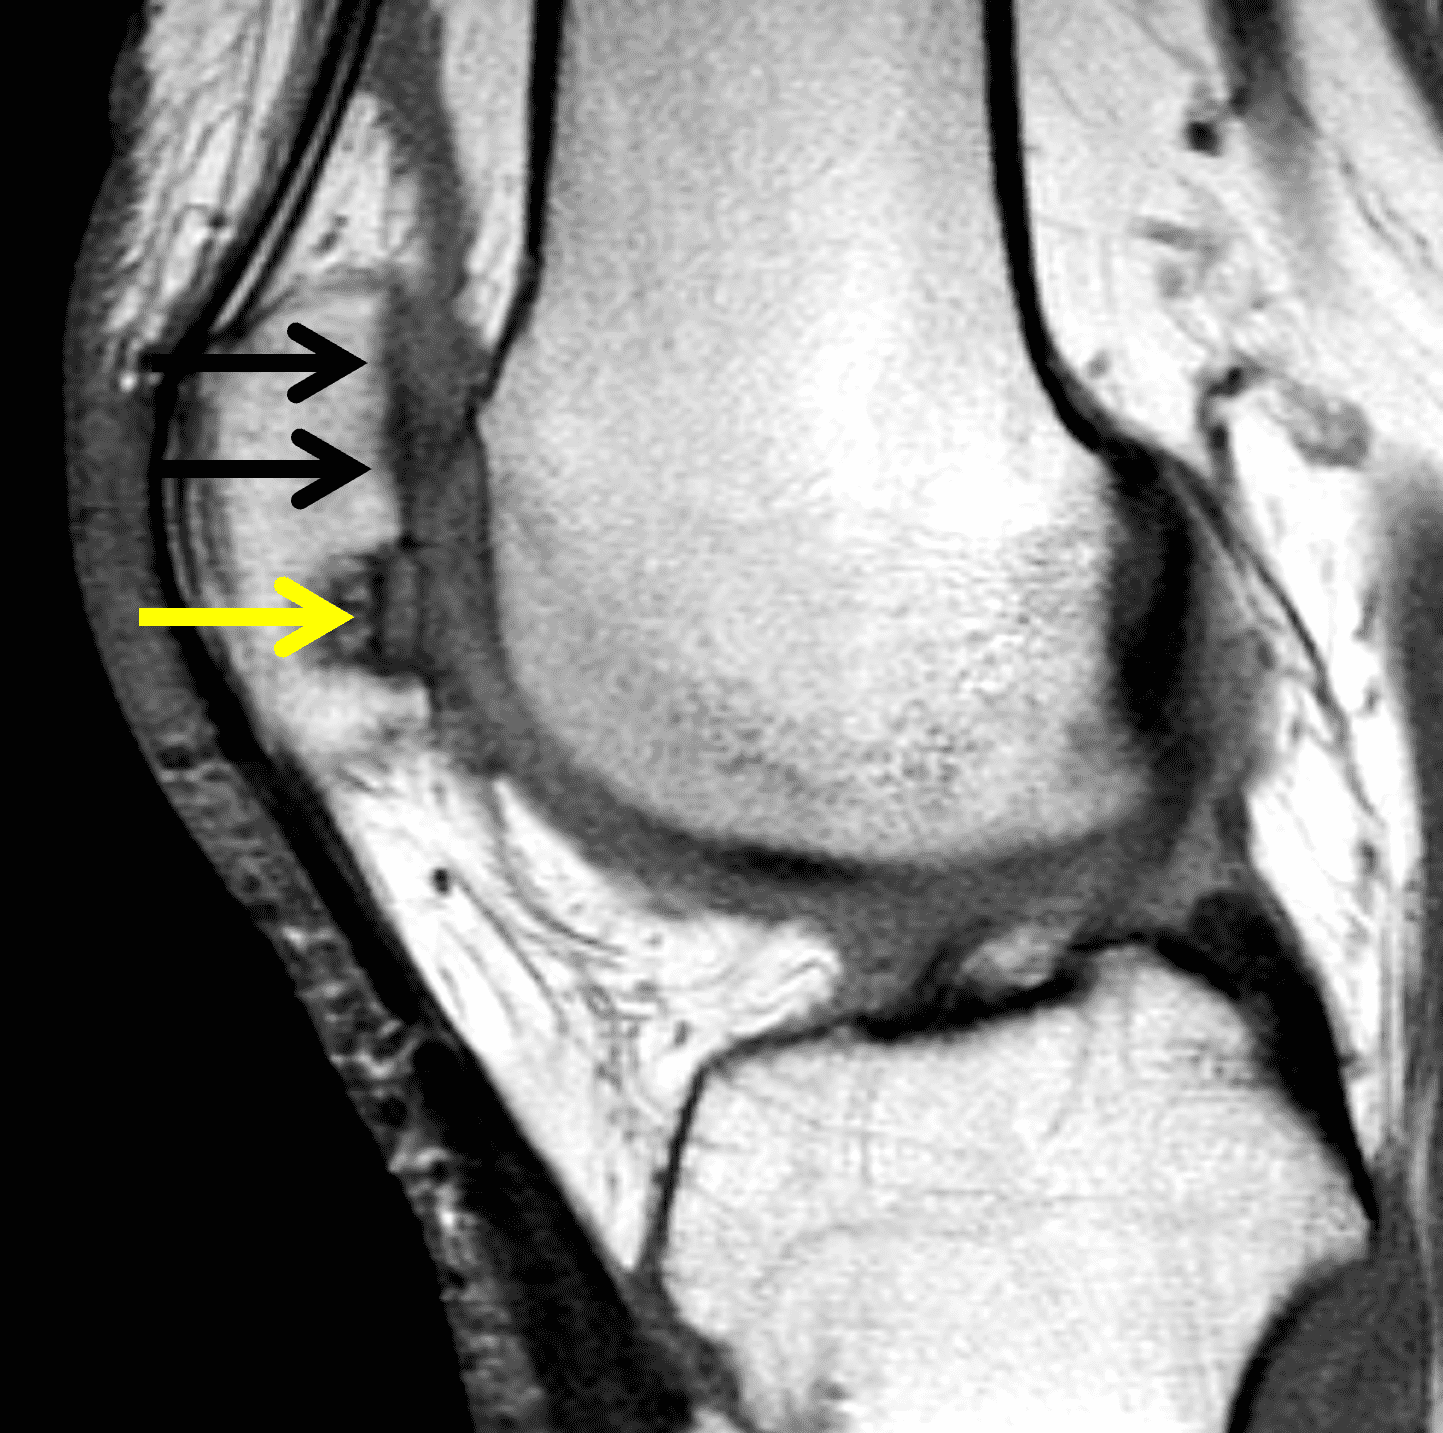

A 32-year-old man suffered a traumatic chondral injury to the medial femoral condyle that was treated with an osteochondral allograft 20 months previously. Representative images from a current knee MRI include (1A) coronal fat-suppressed fluid-sensitive and sagittal (1B) T1-weighted, (1C) proton density-weighted, and (1D) T2-weighted sequences. Are the post-operative MRI findings normal and expected, or abnormal and pathologic? Based on these images, would you characterize the procedure as a success or failure?

Figure 2: (2A) On the coronal image, the margins of the osteochondral graft are faintly visible (arrowheads). Both the graft and underlying bone show mild marrow edema, an expected finding. (2B) The T1-weighted image shows continuity of the marrow in the graft (asterisks) with the underlying bone, indicating osseous integration. A bioabsorbable pin (arrow) used for graft fixation is partly visible. (2C) The proton density-weighted image shows a low signal intensity seam (black arrow) between the native cartilage and transplant, as well as a defect in the subchondral bone plate of the graft (red arrow) where the pin was drilled, both normal findings. (2D) The T2-weighted image shows a smooth, congruent articular surface (arrows), restoring the normal anatomy, and a tiny subchondral cyst. No findings are present to suggest graft failure. The patient’s current symptoms were attributed to pathology elsewhere in the joint (not shown).

The postoperative imaging appearance of osteochondral allografts is similar to autografts (Figure 2).33 The subchondral bone plate of the donor and recipient sites do not have to match, but the articular surface should be congruent. Grafts that fail to incorporate by one year have a poor prognosis. Persistent marrow edema (beyond 12 months), a thick graft interface containing cysts or fluid, and subsidence of the graft are associated with poor osseous healing and worse outcomes. Extensive host marrow edema and severe synovitis may be a clue to immunologic rejection of the graft (Figure 18).21, 34